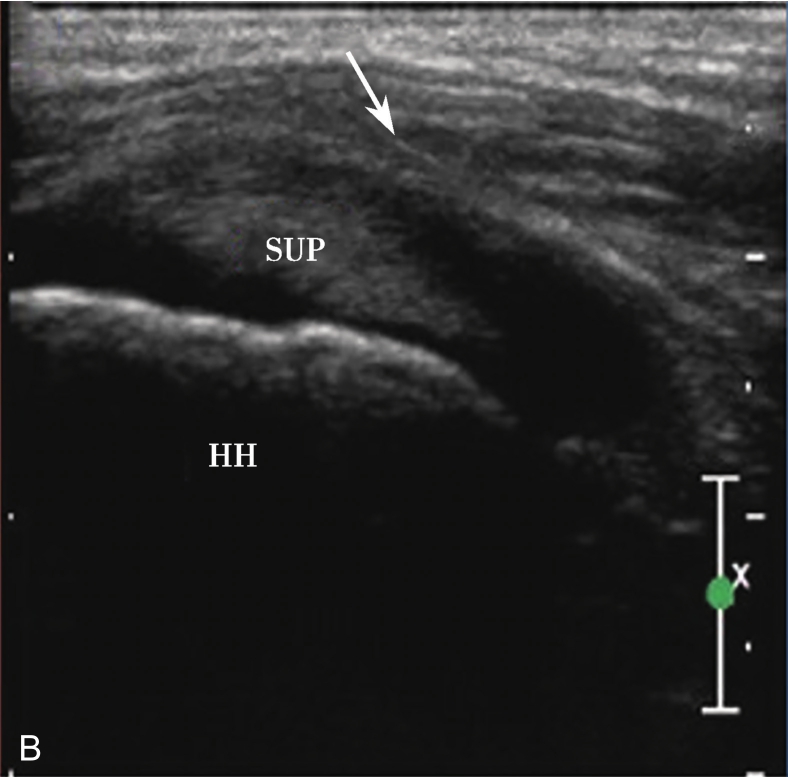

A.超声引导下滑囊内注入超声造影剂后,滑囊呈线状高增强(箭头);B.注入造影剂后的滑囊(箭头),冈上肌腱(SUP)连续性好,未见撕裂,HH:肱骨头

A.超声引导下滑囊内注入超声造影剂后,滑囊呈线状高增强,肌腱内可见局限性高增强,提示肌腱滑囊面部分撕裂(箭头);B.二维超声显示冈上肌腱(SUP)回声不均匀(箭头),但未见明显撕裂,HH:肱骨头